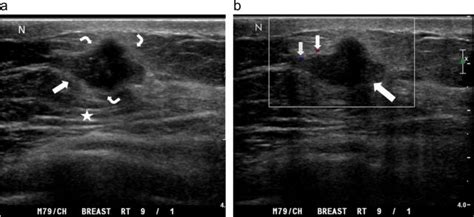

男性乳腺发育症是由于青春期内分泌紊乱,或者是由于服用含激素的药物所致,一般根据病史及体格检查就可确诊,超声可以辅助诊断组织的性质。乳房增大的组织可以是腺体也可以是脂肪组织,有一定的癌变风险,因此需要手术治疗。对于以脂肪增多的患者来说,可以采用吸脂来治疗,如果发育的组织为腺体,就需要手术切除。